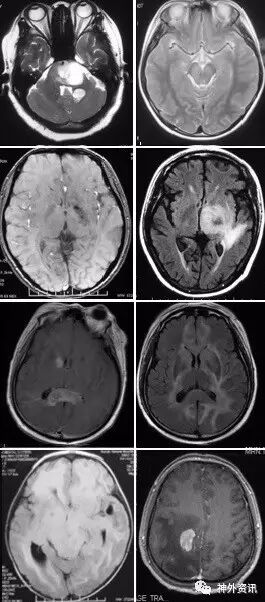

(重要申明:以下每个部分会配磁共振图片,因疾病和影像之间存在同病异象、同像异病,为避免误导,图片不标注疾病,其各自鉴赏,另其中的部分图片来源于网络,有疑问可与本人联系)

脱髓鞘,多发性硬化(MS)、视神经脊髓炎(NMO)、急性播散性脑脊髓炎(ADEM)、MOG相关性脱髓鞘病变、自身免疫性脑炎、CNS血管炎、神经系统结节病、Susac's Syndrome、Clippers’综合症、桥本氏脑病等。还有如急性、亚急性的放疗损伤等。

各种肿瘤,如胶质瘤、淋巴瘤、脑膜瘤、血管内淋巴瘤,生殖细胞瘤、各种转移瘤、心房粘液瘤等。神经纤维瘤病也可在中枢出现影像学上类似脱髓鞘的病变。